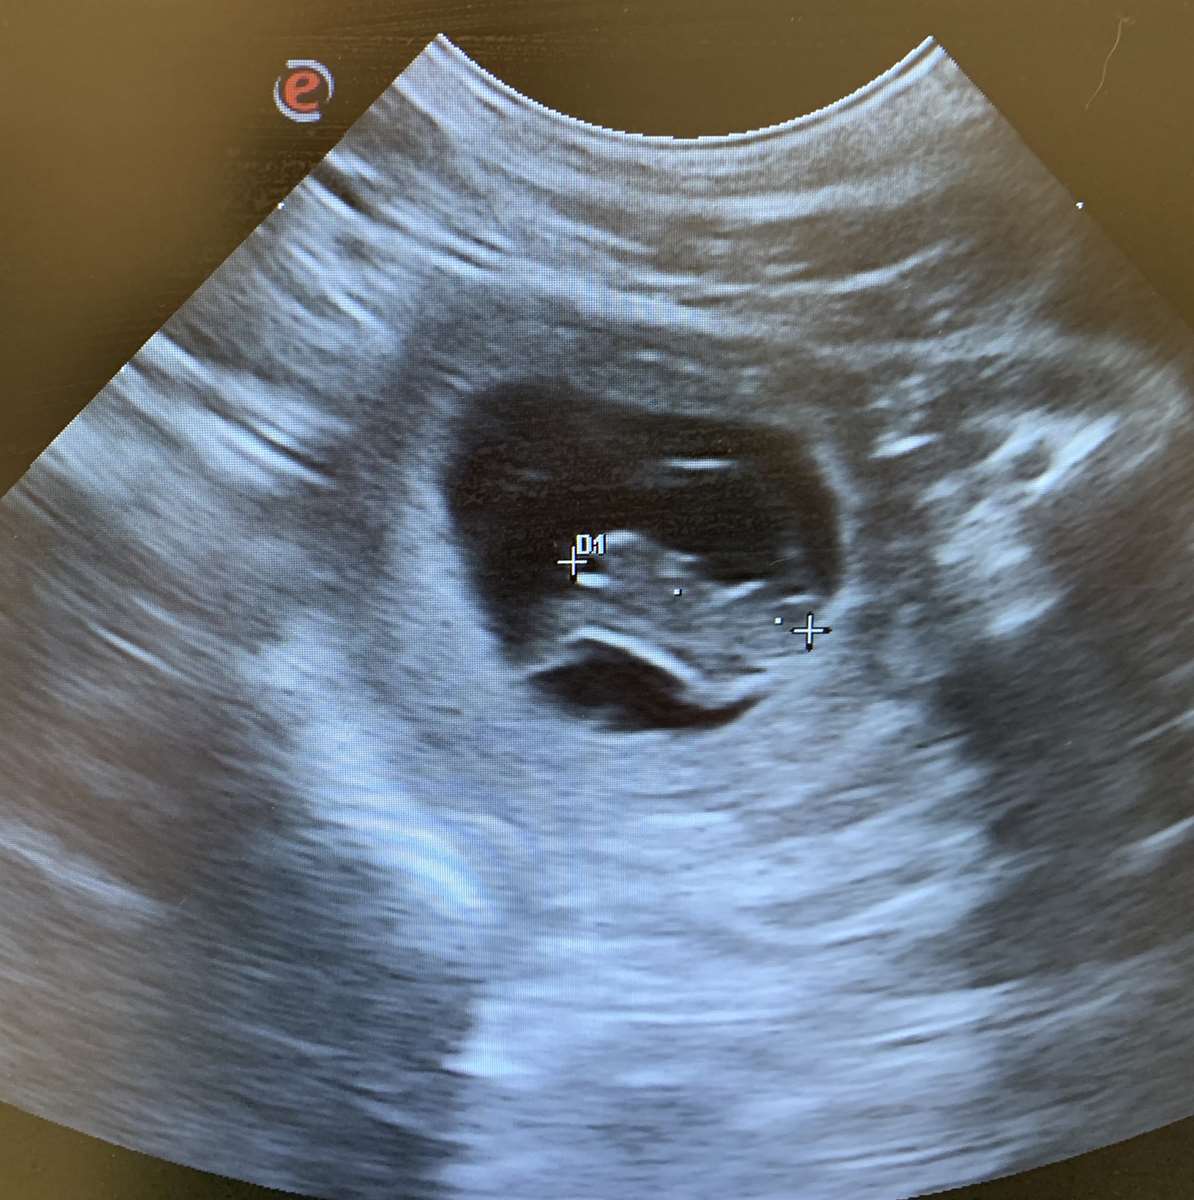

En drægtighedsscanning af hund kan give et fantastisk indblik i fostrenes udvikling.

Fra ca. 18-19 dage efter ægløsningen kan de kommende hvalpe ses som små væskeblærer i uterus (livmoderen).

Fra ca. dag 23-35 kan fostrene tælles (jo flere hvalpe der er desto sværere er det at give et præcist antal) og fra dag ca. 23 kan vi se fostrenes hjerteslag.

Igennem hele drægtigheden kan fostrenes udvikling følges i stor detalje. Med baggrund i vores store specialviden og erfaring med ultralydsscanning af rigtigt mange drægtige tæver, kan vi ud fra hvalpenes udviklingsstadie med en ultralydsscanning datere hvornår tæven har forventet termin. Dette gør vi bl.a. ved at se på specifikke strukturer og fostrenes kraniemål.